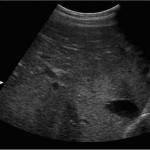

Различные признаки изменения печени обнаруженные на УЗИ свидетельствуют о наличии различных заболеваний вызвавших эти изменения. Диффузные изменения печени обычно характеризуются снижением эхогенности органа. Повышение ее уровня свидетельствует об образовании в печени уплотнений.

Что это за исследование

УЗИ печени – это разновидность диагностических процедур, проводимых при помощи взаимодействия ультразвука с тканями и биологическими средами организма, результатом которого становится возможность изучения структуры и некоторых функциональных особенностей печени и путей системы желчеотделения. Это значит, что при помощи УЗИ печени можно получить достоверную и важную информацию об индивидуальных особенностях и параметрах этого органа.

Печень нельзя рассматривать, как изолированный орган пищеварительного тракта. Она анатомически и функционально связана с системой протоков, по которой происходит отток желчи, и крупными сосудами, осуществляющими процессы кровообращения в ней. Печень, являясь крупны органом, состоящим из паренхиматозной ткани, протоков желчной системы и сосудистых образований, имеет достаточно удобное анатомическое расположение в брюшной полости. Все это создает предпосылки для хорошей визуализации структур и изучения особенностей их строения (размеров, диаметра, просвета и пр.) В ходе УЗИ можно получить информацию о:

Дополнительные показатели здоровой печени, характеризующие нормальные данные УЗИ такие: четкие, ровные края и контуры, однородная эхогенность и структура, отсутствие дополнительных и опухолевых образований.

Диффузные поражения печени на УЗИ

1. Липидный гепатоз — отложение жировых вакуолей в гепатоцитах. На УЗИ выявляют диффузное увеличение сигнала, уплотнение органа.

Как вы поняли, УЗИ (метод ультразвуковой диагностики) брюшной полости позволяет узнать о наличии любых патологических состояний, является одним из главных методов терапии. Стоит заметить, что изменения в паренхиме – не диагноз, а всего лишь признаки, которые помогут определить, какое же заболевание протекает в организме.